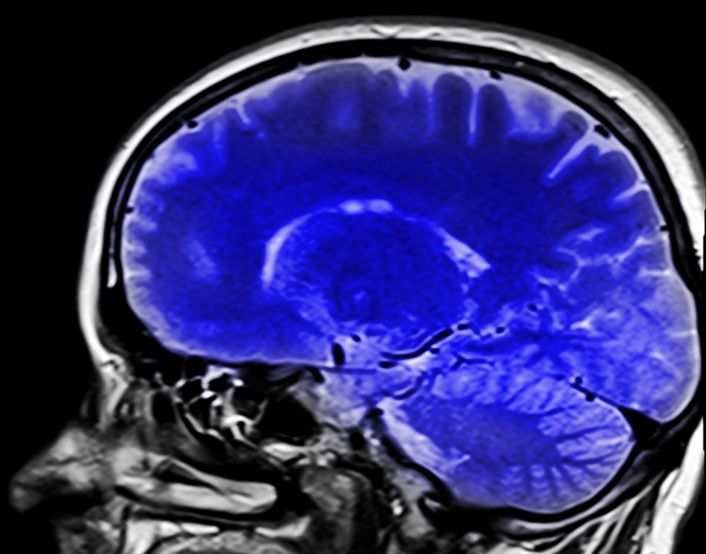

치매란 치매라는 자체가 하나의 질병을 뜻하는 것은 아니며, 다양한 원인들로 인한 뇌 손상에 의하여 기억력을부터 인지기능 장애 등이 발생하여 예전 수준의 일생생활을 유지할 수 없는 상태를 포괄적으로 의미하느 단어입니다.

치매 증상은 뇌 손상으로 인하여 나타나는 것이기 때문에 뇌의 손상 부위가 어디인가에 따라 다른 증상이 나타날 수 있습니다.

전두엽이 손상되었으면 판단력이나 성격에 이상이 오게 되고, 두정엽이 손상되면 시간이나 계산, 공간 능력이 떨어지게 되며, 측두엽이 손상되면 언어 능력이나 기억이 떨어지며, 후두엽에 손상되었을 때는 시각 능력에 이상이 옵니다.

치매 검사나 등급 판정은 신경과에서 받을 수 있으며, 치매 검사는 CT로 뇌 촬영 후 인지 능력 확인 등으로 치매 검사가 진행되며,